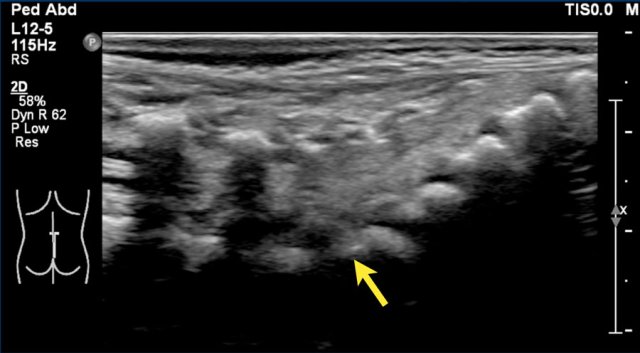

This image is of a newborn girl with an anorectal malformation.

The distal sacrum below S4 is absent (arrow).

Since an anorectal malformation is frequently associated with spinal pathology, an ultrasound was performed.

If a plain film of the vertebral column demonstrates an anomaly of the sacrum, there is a 50% change of an intraspinal anomaly.

In most cases there is a low ending tethered cord.

In some cases however the cord ends at the normal position, but is deformed.

This is a so-called blunt cord terminus.

There is generally a wedge-shaped ending in which the dorsal side reaches further caudally than the ventral side.

Continue with the ultrasound.

Ultrasound of the spine shows a blunt cord terminus at T12-L1.

A blunt cord terminus is a sign of caudal regression syndrome characterized by abnormal development of the lower end of the spine.

On ultrasound the absent coccyx is also visible.